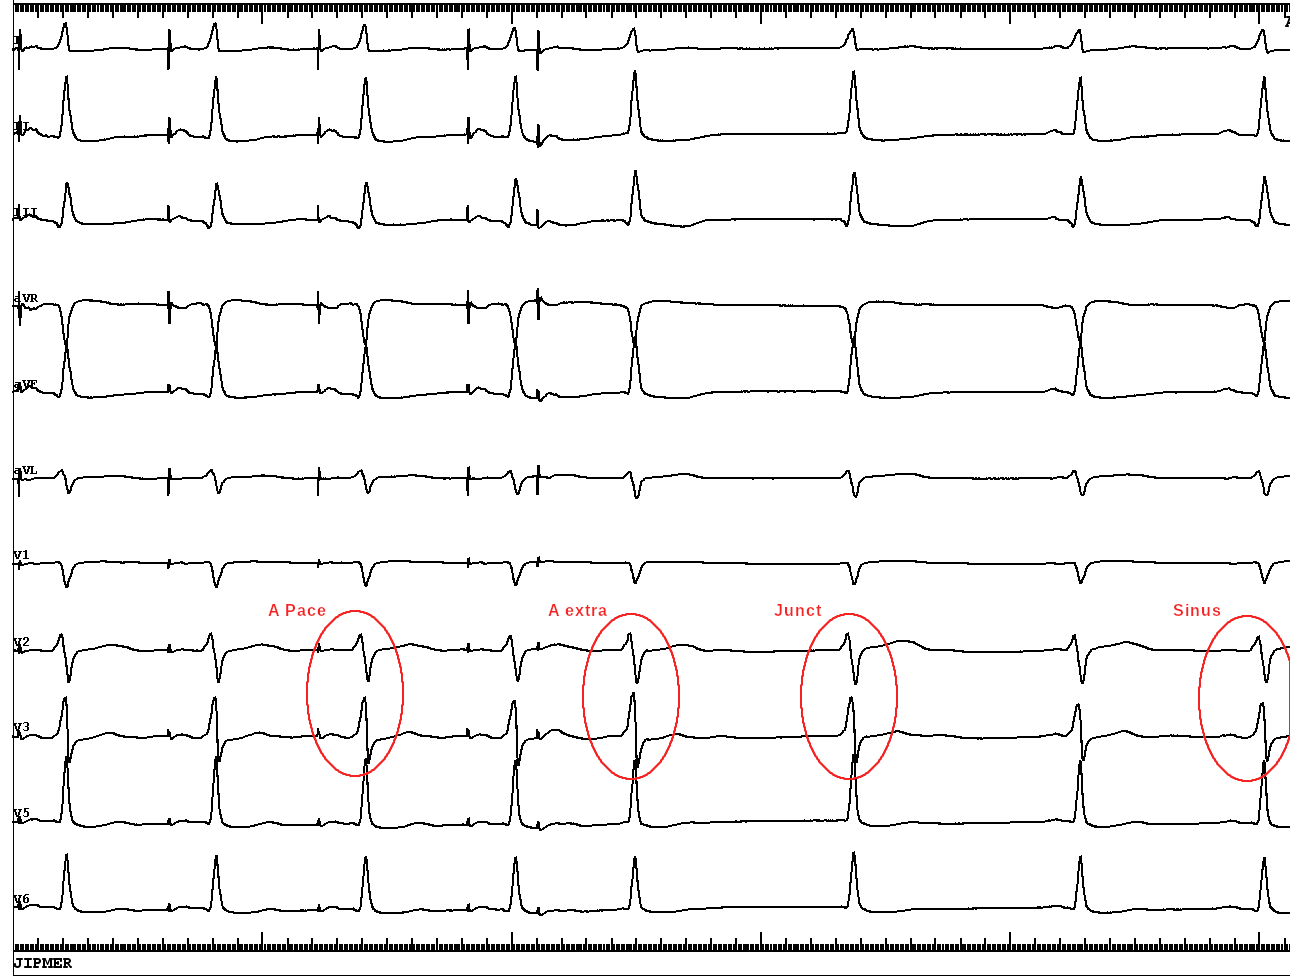

Case 1 - SVT in 42 F

tachy.jpg

Entrainment from base (cPPi-TCL 80)

entrainment_base.jpg

Entrainment from apex (PPI-TCL 96)

entrainment.jpg

PVC on His

pvc.jpg

Diagnosis

• Concealed nodoventricular AP

• Orthodromic tachycardia

• Successful ablation at RIE